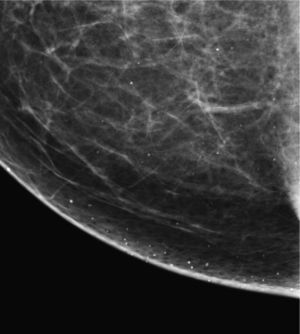

Las calcificaciones indeterminadas, como las demás, pueden ocupar una zona extensa de la mama (fig. 8), ser segmentarias (cuando ocupan un segmento) o estar agrupadas (fig. 9)6.

Como su nombre indica, son calcificaciones que hacen sospechar un proceso neoformativo subyacente.

Pueden aparecer de forma aislada o asociadas a una masa palpable o a una distorsión del parénquima mamario.